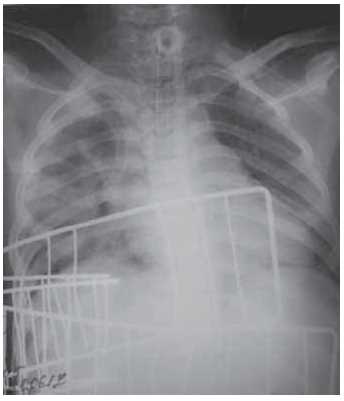

Control radiography of the chest organs revealed positive dynamics in the form of increased pneumatization of the right lung (Figure 5).

Fig. 5. An overview radiograph of the thoracic organs 6 days after the operation